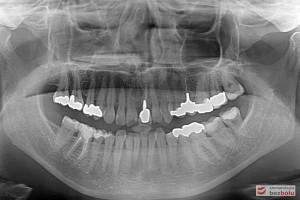

Do naszej placówki zgłosiła się starannie planująca swoje działania Europejka, mieszkająca na stałe w Kotlinie Jeleniogórskiej. Jej oczekiwania dotyczyły bardzo metodycznie zaplanowanego planu leczenia. Celem jaki postawiła przed naszym zespołem lekarzy było wyeliminowanie wszystkich wątpliwych i nierokujących wypełnień, a także poprawa estetyki w zakresie lewego siekacza centralnego w szczęce. Został rozpisany blisko dwuletni plan wymiany zużytych i nieszczelnych wypełnień amalgamatowych i kompozytowych. Zaplanowano również przygotowanie endodontyczne wybranych zębów w szczęce i żuchwie, a także zaopatrzenie w inlay’e porcelanowe i korony ceramiczne wykonane w systemie e-max.